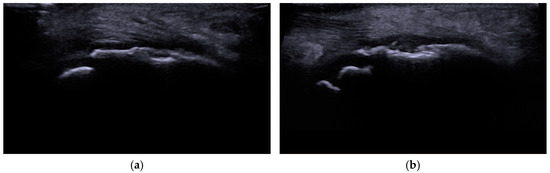

- Draghi, F.; Danesino, G.M.; Coscia, D.; Precerutti, M.; Pagani, C. Overload syndromes of the knee in adolescents: Sonographic findings. J. Ultrasound 2008, 11, 151–157. [Google Scholar] [CrossRef]

- Valentino, M.; Quiligotti, C.; Ruggirello, M. Sinding-Larsen-Johansson syndrome: A case report. J. Ultrasound 2012, 15, 127–129. [Google Scholar] [CrossRef] [PubMed]